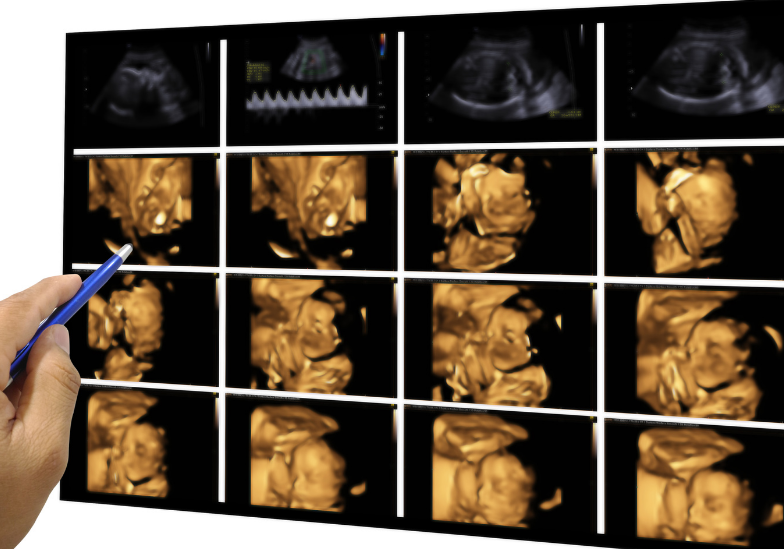

Khám sàng lọc trước sinh là một trong những bước quan trọng mà mọi thai phụ nên thực hiện để đảm bảo sức khỏe cho cả mẹ và bé trong suốt thai kỳ. Đây là quy trình giúp phát hiện sớm các nguy cơ dị tật bẩm sinh, bệnh lý di truyền hoặc các vấn đề sức khỏe tiềm ẩn của thai nhi.

Khám sàng lọc trước sinh là tập hợp các xét nghiệm và kỹ thuật chẩn đoán được thực hiện trong suốt thai kỳ nhằm đánh giá sức khỏe của thai phụ cũng như phát hiện sớm các bất thường ở thai nhi.

Quy trình này thường bao gồm siêu âm thai và các xét nghiệm máu không xâm lấn, giúp cung cấp thông tin quan trọng mà không gây ảnh hưởng đến thai nhi. Với sự phát triển của y học hiện đại, khám sàng lọc trước sinh không chỉ là một khuyến nghị mà đã trở thành bước thiết yếu để đảm bảo an toàn cho cả mẹ và bé.